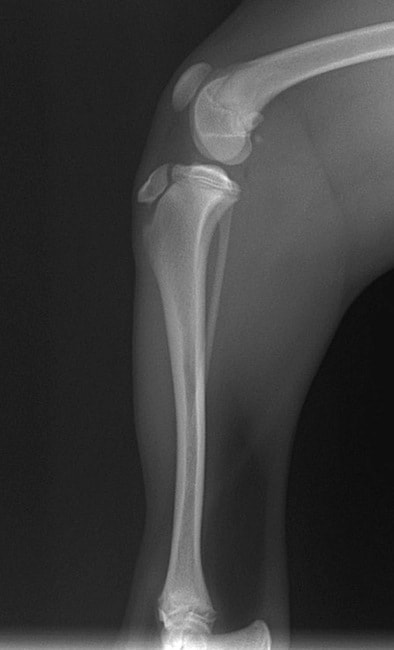

■ 症例24 キャバリア 7か月

左右膝蓋骨内方脱臼(左:グレードⅣ 右:グレードⅢ)

以前から左右後肢の跛行が認められ、整形外科学的検査・レントゲン検査により左右の膝蓋骨脱臼が認められた。症状が重度である左膝の膝蓋骨脱臼整復術を行った。外科手技は縫工筋及び内側広筋の解放、脛骨粗面の外側転位、滑車ブロック形造溝術、内外側関節方の縫縮を実施した。術後一か月時点で、左の膝蓋骨は安定しており経過は良好である。

本症例は成長期における重度の膝蓋骨脱臼であり、術後の再発の可能性もあるため、経過をしっかりと観察していく必要がある。また、今回手術を実施していない右膝に関しても経過を観察し、手術を検討していくこととする。